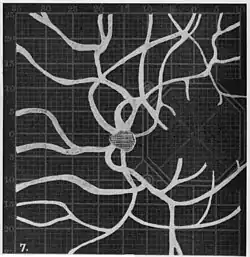

Angioscotomas were first discovered and mapped out by John Norris Evans (1891-02-28--1953-04-08)[2] in 1926, who coined the term angioscotometry to describe the painstaking charting of the scotoma of the retinal blood vessels by manual perimetry. He seated each subject in a seat in a dark setting, and tested whether they could see a tiny bright test object placed at various locations.[3] Using a 1.5 mm white disk, Evans reported intricate branch‑like scotomas that mirrored the arteries and veins emerging from the optic disc, with a full map requiring up to 2 hours to complete. He plotted this for subjects under various conditions, such as while holding breath, with glaucoma, etc. A year later, he confirmed that only short stump‑like scotomas had been noticed previously, some further data plotted with a smaller 1 mm stimuli, and under varying conditions on the subject.[4] He published a monograph on this in 1938 in which he described its use in assisting diagnosis of various conditions, such as retinal edema, glaucoma, optic neuritis, etc.[5]

1. Pressure on globe shows only stumps of large vessels. 2. Holding the breath causes similar effect; also 3. Holding the head low. 4. Pressure on opposite eye widens arteries and still more veins, 5. Pressure on the carotid produces no definite effect. 6. Looking thru red glass brings out finer vessels. -